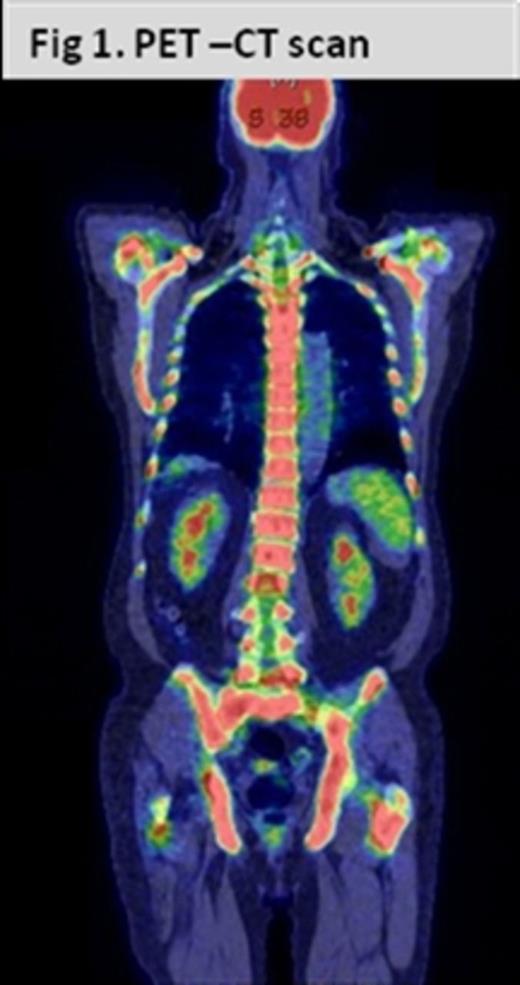

PET-CT scan showed marked increase in metabolic activity diffusely involving the axial skeleton but no metabolically active lymphadenopathy or extramedullary disease, no destructive or lytic lesions were found [Fig.1].